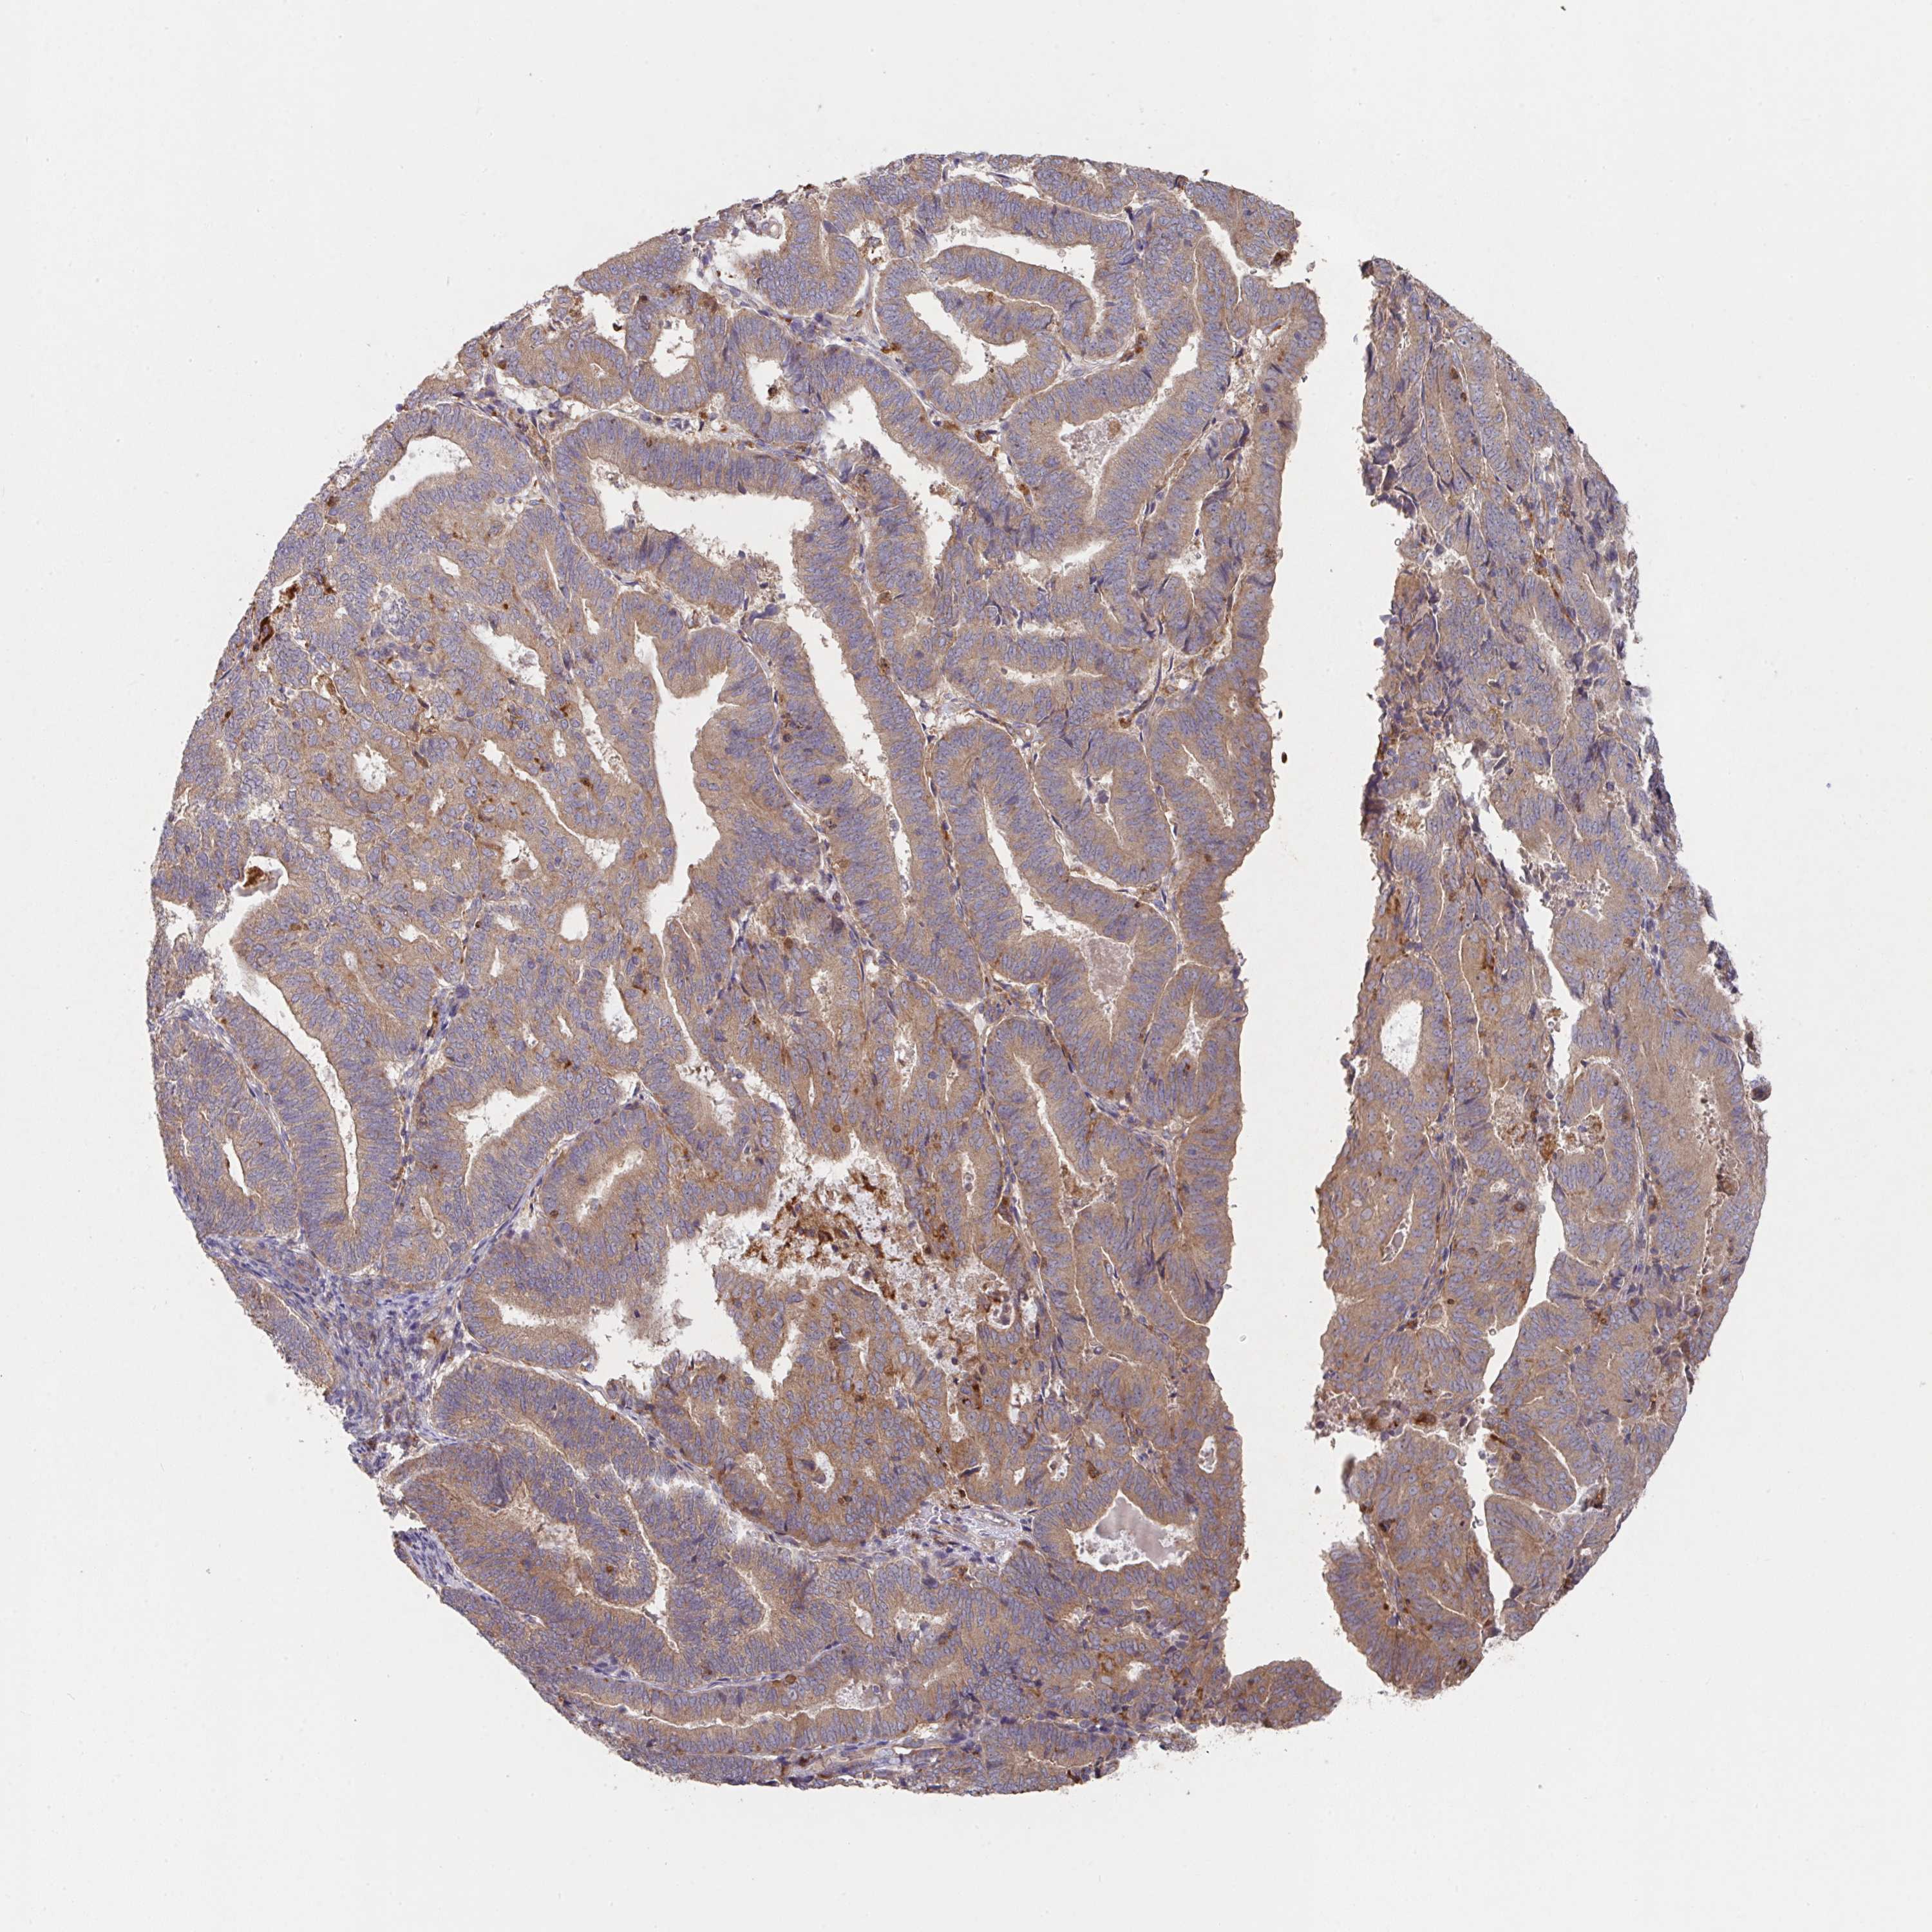

ENDOMETRIAL CANCER - Protein expressioni

A mouse-over function shows sample information and annotation data. Click on an image to view it in a full screen mode. Samples can be filtered based on level of antibody staining by selecting one or several of the following categories: high, medium, low and not detected. The assay and annotation is described here.

Note that samples used for immunohistochemistry by the Human Protein Atlas do not correspond to samples in the TCGA dataset.

Antibody stainingi

Antibody staining in the annotated cell types in the current human tissue is reported as not detected, low, medium, or high, based on conventional immunohistochemistry profiling in selected tissues. This score is based on the combination of the staining intensity and fraction of stained cells.

Each image is clickable and will lead to virtual microscopy that enables deeper exploration of all samples and also displays staining intensity scores, fraction scores and subcellular localization as well as patient and tissue information for each sample.

Antibody HPA053217

Staining

High

Medium

Low

Not detected

Intensity

Strong

Moderate

Weak

Negative

Quantity

>75%

75%-25%

<25%

None

Location

Nuclear

Cytoplasmic/membranous

Cytoplasmic/membranous,nuclear

Adenocarcinoma, NOS